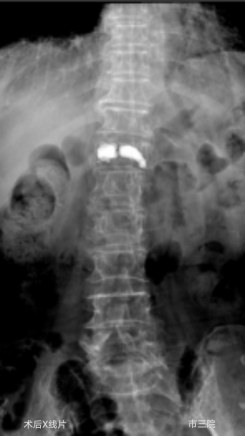

外二科收治了一位82岁的老年女性患者,患者摔倒后因腰部疼痛不能下床活动,在家长期卧床5个月,期间外用膏药,效果不佳,老人虽八十多岁,但受伤前身体硬朗,自己能够洗衣、做饭、赶集等,自从摔伤后不见好转卧病在床,子女们轮流照顾老人,打破了原本平静的生活,眼见老人下不了床子女们心急如焚,四处打听创伤小恢复快的治疗办法,经人介绍来到我院外二科就诊,磁共振检查显示患者胸12椎体压缩性骨折,椎体压缩性骨折已经5个月了仍未愈合,已经形成kummell 病,骨折基本不能愈合,此病首选经皮穿刺骨水泥注射椎体成形术治疗,创伤小、可迅速恢复自理生活,经与患者及家属沟通后同意手术治疗,就诊当天就办理了住院,住院后赵东主任医师对老人进行了全面查体,对老人家原本患有“冠心病、糖尿病”,积极联系内科会诊,完善术前检查做好充分术前准备。术中C型臂准确定位后,局麻下5mm皮肤切口,赵东主任医师顺利打入椎体骨水泥,韩克伟医生询问患者有无不适,患者诉腰部疼痛症状消失,术后第二天,患者佩戴胸腰护具下床独立行走,露出了久违的笑容。